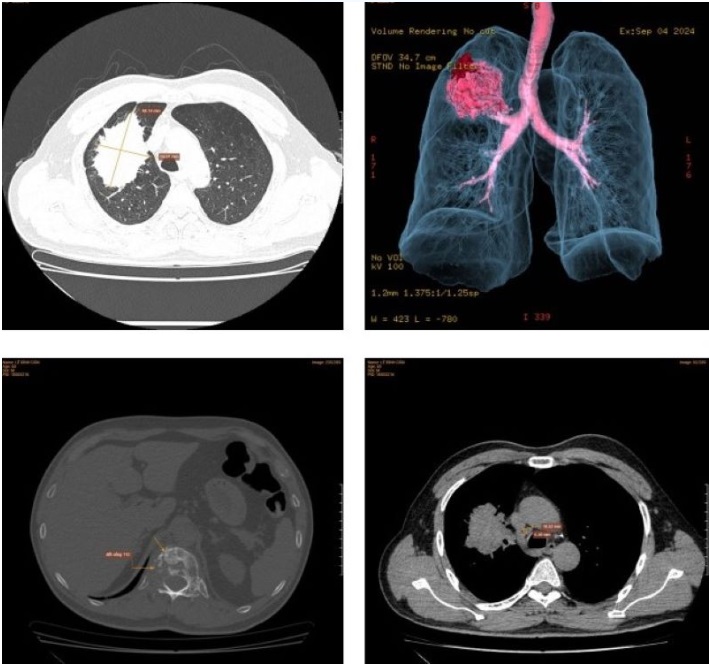

Kết quả chụp cắt lớp vi tính phát hiện bất thường. Ảnh: BVCC

Lo lắng về tình trạng sức khỏe, ông D đã tới Phòng khám Medlatec Gò Vấp (TP.HCM) để khám. Qua thăm hỏi và khám bệnh, bác sĩ chỉ định bệnh nhân làm các xét nghiệm, chẩn đoán hình ảnh cần thiết. Kết quả chụp cắt lớp vi tính phát hiện tổn thương "ăn mòn" xương đốt sống (D12L1) điển hình của một tổn thương thứ phát (di căn).

Nghi ngờ có khối u ác tính, bác sĩ đã chỉ định bệnh nhân chụp CT phổi liều thấp và phát hiện tổn thương u thùy trên phổi phải, kích thước lớn, đường bờ tua gai co kéo màng phổi vùng tương ứng quanh u. Dựa vào các kết quả trên, bệnh nhân được chẩn đoán u thùy trên phổi phải, theo dõi ung thư phổi di căn. Bệnh nhân đã được chuyển viện tới viện Chợ Rẫy thực hiện quá trình điều trị theo chuyên khoa.